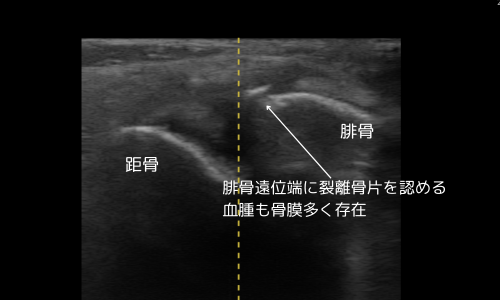

腓骨遠位端に裂離した骨片を確認。

小児に多い裂離骨折であり、レントゲンでは見逃されることもあるタイプです。

9月下旬(施療初期)